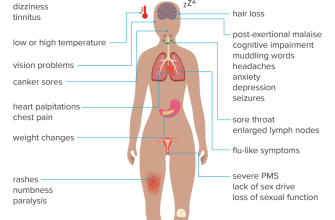

Symptom Database

Learning disabilities are a common issue that affects

Lethargy, also known as fatigue or tiredness, is a